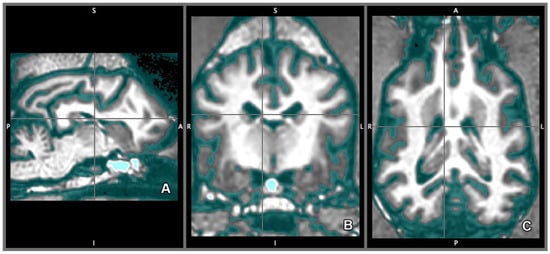

2.5. Morphology and Size of the Measured Brains